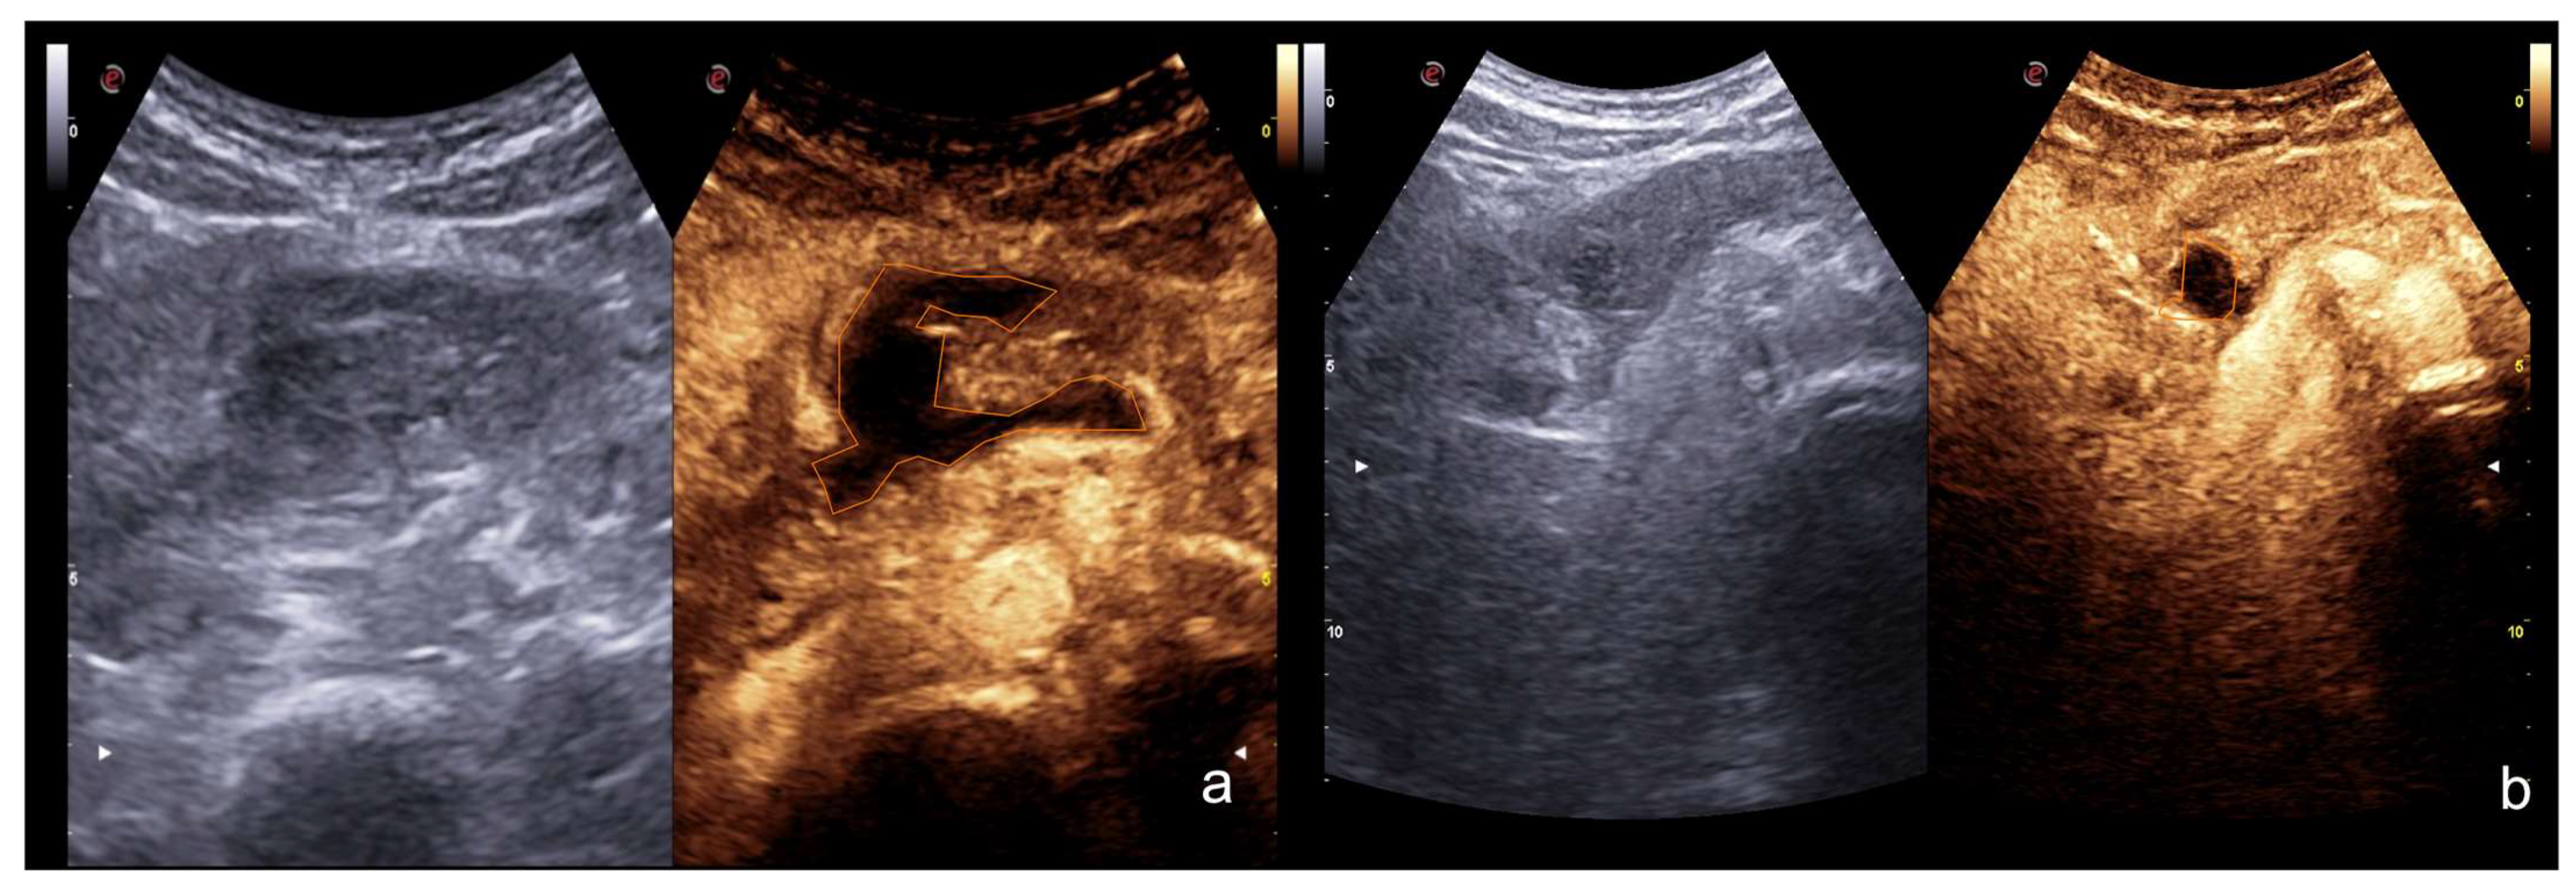

2.3.2. Vascular Injuries

- Active bleeding:

- Contained vascular injuries:

| 2–6 min | Venous-late phases: distribution of the contrast in the whole organ. Best time to depict parenchymal injuries. |

| Flash mode | Destruction of bubbles and possibility to re-evaluate an area of interest. |